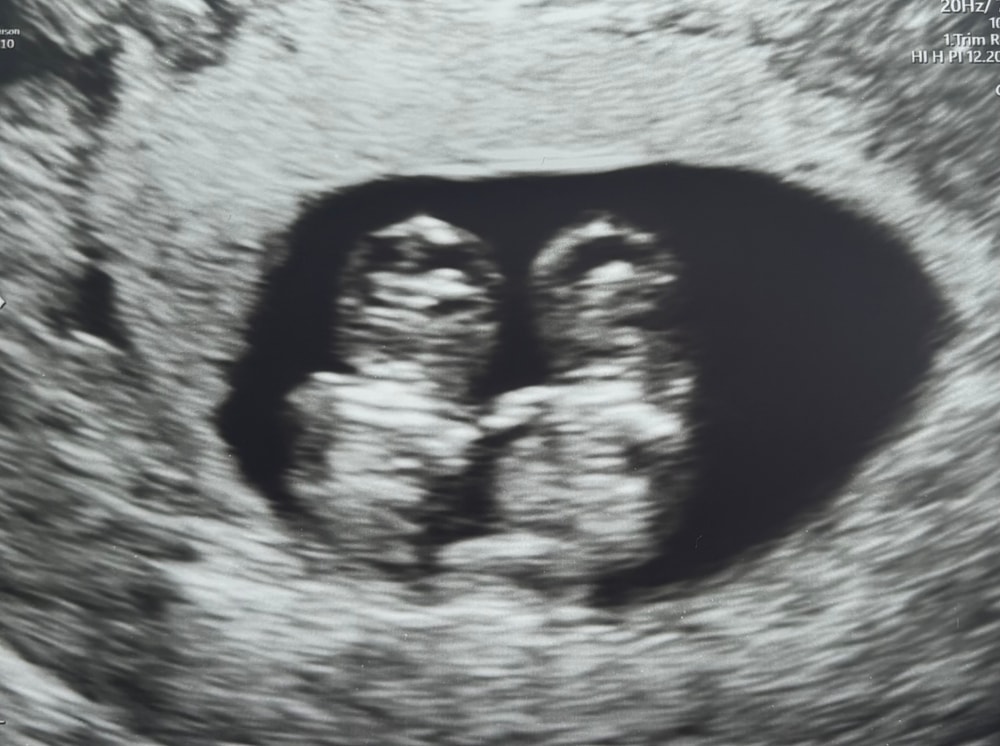

Mari, смотря чем не разошлись близнецы. Бывают органы на двоих одни, там конечно сразу погибнут, а бывают просто спинками, или ножками, там другой может жить. У меня малыши были тоже всегда близко. Но врач четко увидела, что они раздельны. После родов я их посмотрела. Да два человечка, у каждого всё своё, всё сформировано. Мои замерли на 14 недели… Я тоже не могла понять почему, обычно если поломка ДНК то замирают на ранних сроках, но мои вот дожили до такого… Мои малышки… Изображение Изображение